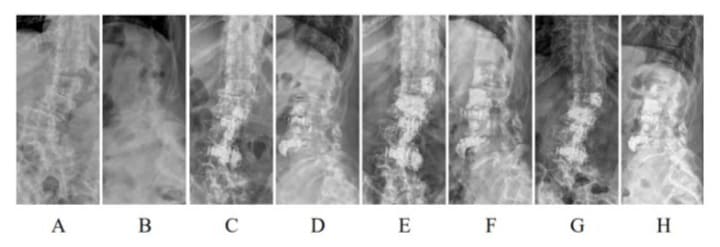

Figure 10: A 79-year-old female with degenerative scoliosis 40° and lumbar kyphosis 34° (A, B) underwent PIBC. Immediate postoperative scoliosis was 5° and lumbar lordosis was 13° (C, D). Eighteen months later, the scoliosis was 3° and lumbar lordosis was 5° (E, F). Asymptomatic cement leakage was observed on the ventral side of the L1 vertebral body.

Figure 11: A 75-year-old female with degenerative scoliosis of 43° and lumbar lordosis of 36° (A, B) underwent L2/4 OIBC. Immediate postoperative scoliosis was 5° and lumbar lordosis was 48° (C, D). She underwent L1/2 PIBC 41 days later. (E, F), which was wellmaintained at the final follow-up at one year (G, H).